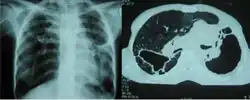

Fibrothorax caused by infection with M lentiflavum.